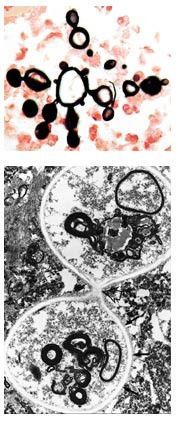

Mikroskopisk undersøkelse . Frysesnittet viste en abscessvegg med subakutt betennelse med parasitter/sopp. Det innstøpte materialet viste abscessdanning med subakutt betennelse med granulomer, multinukleære kjempeceller og rikelig med soppelementer. Soppelementene hadde en tydelig membran med tendens til dobbeltbrytning i polarisert lys. Spesialfarging (Grocotte) viste at de største soppelementene var 30 – 40 µ m i diameter. Langs hele omkretsen av slike morelementer var det knoppskyting av nye elementer. Disse datterelementene hadde smalhalset (”narrow based”) forbindelse til morelementet. Dette vekstmønsteret gir opphav til strukturer som minner om skipsratt (fig 2a). Elektronmikroskopisk undersøkelse viste også smalhalset knoppskyting (fig 2b). Disse strukturelle trekkene er diagnostisk for Paracoccidioides brasiliensis. Identifikasjon av soppen ved et referanselaboratorium bekreftet diagnosen.

Klinisk opptrer sykdommen i to former: en akutt (subakutt) juvenil form (5 % av tilfellene) og en kronisk form (95 % av tilfellene) (1, 3). I begge tilfeller er det ofte svekket cellulær immunitet hos pasienten (1 – 3). Den juvenile formen har et raskere forløp og er mer alvorlig enn den kroniske (1). I likhet med tuberkulose kan latensperioden fra primærinfeksjon til klinisk sykdom være svært lang. Det er beskrevet tilfeller der det har gått 60 år fra pasienten hadde forlatt det endemiske området til symptomene oppstod. I vårt tilfelle var det antakelig gått 23 år fra pasienten siste gang var i det endemiske området. Den kroniske formen rammer langt flere menn enn kvinner. Lungene er ofte affisert (90 % av tilfellene), men det er ikke uvanlig med lesjoner i slimhinner, hud, lymfeknuter og binyrer. Det er også rapportert at bein, øye og sentralnervesystem kan være involvert (1 – 4). Histologisk sees granulomatøs betennelse eller abscesser som ved andre soppinfeksjoner. Spesifikk diagnose stilles på det distinkte utseendet til vevsformen av Paracoccidioides brasiliensis (fig 2a, b). Nevroradiologisk likner sykdommen tuberkulose, da begge tilstandene kan manifestere seg som velavgrensede pseudotumorer og som fortykkede hjernehinner basalt (4). Uten behandling er dødeligheten høy, men de fleste pasienter responderer på spesifikk terapi (1 – 4).